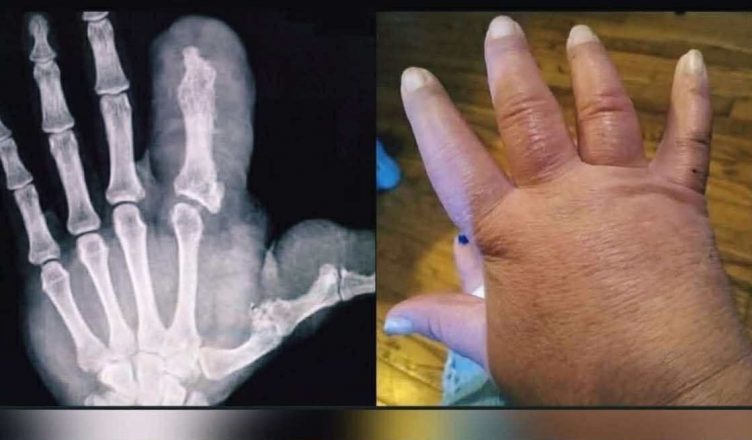

Od narození jí palec rostl rychleji než zbytek ruky. Zpočátku se to zdálo triviální – dětská vrtoch, o které se diskutovalo s úsměvem. Ale rok co rok se kůže napínala, nehet se stal jako malá mušle a ruka ztrácela svůj známý tvar. Lékaři tomu říkali slovo, které znělo téměř cize – makrodaktylie. Vysvětlovalo to všechno a zároveň nic.